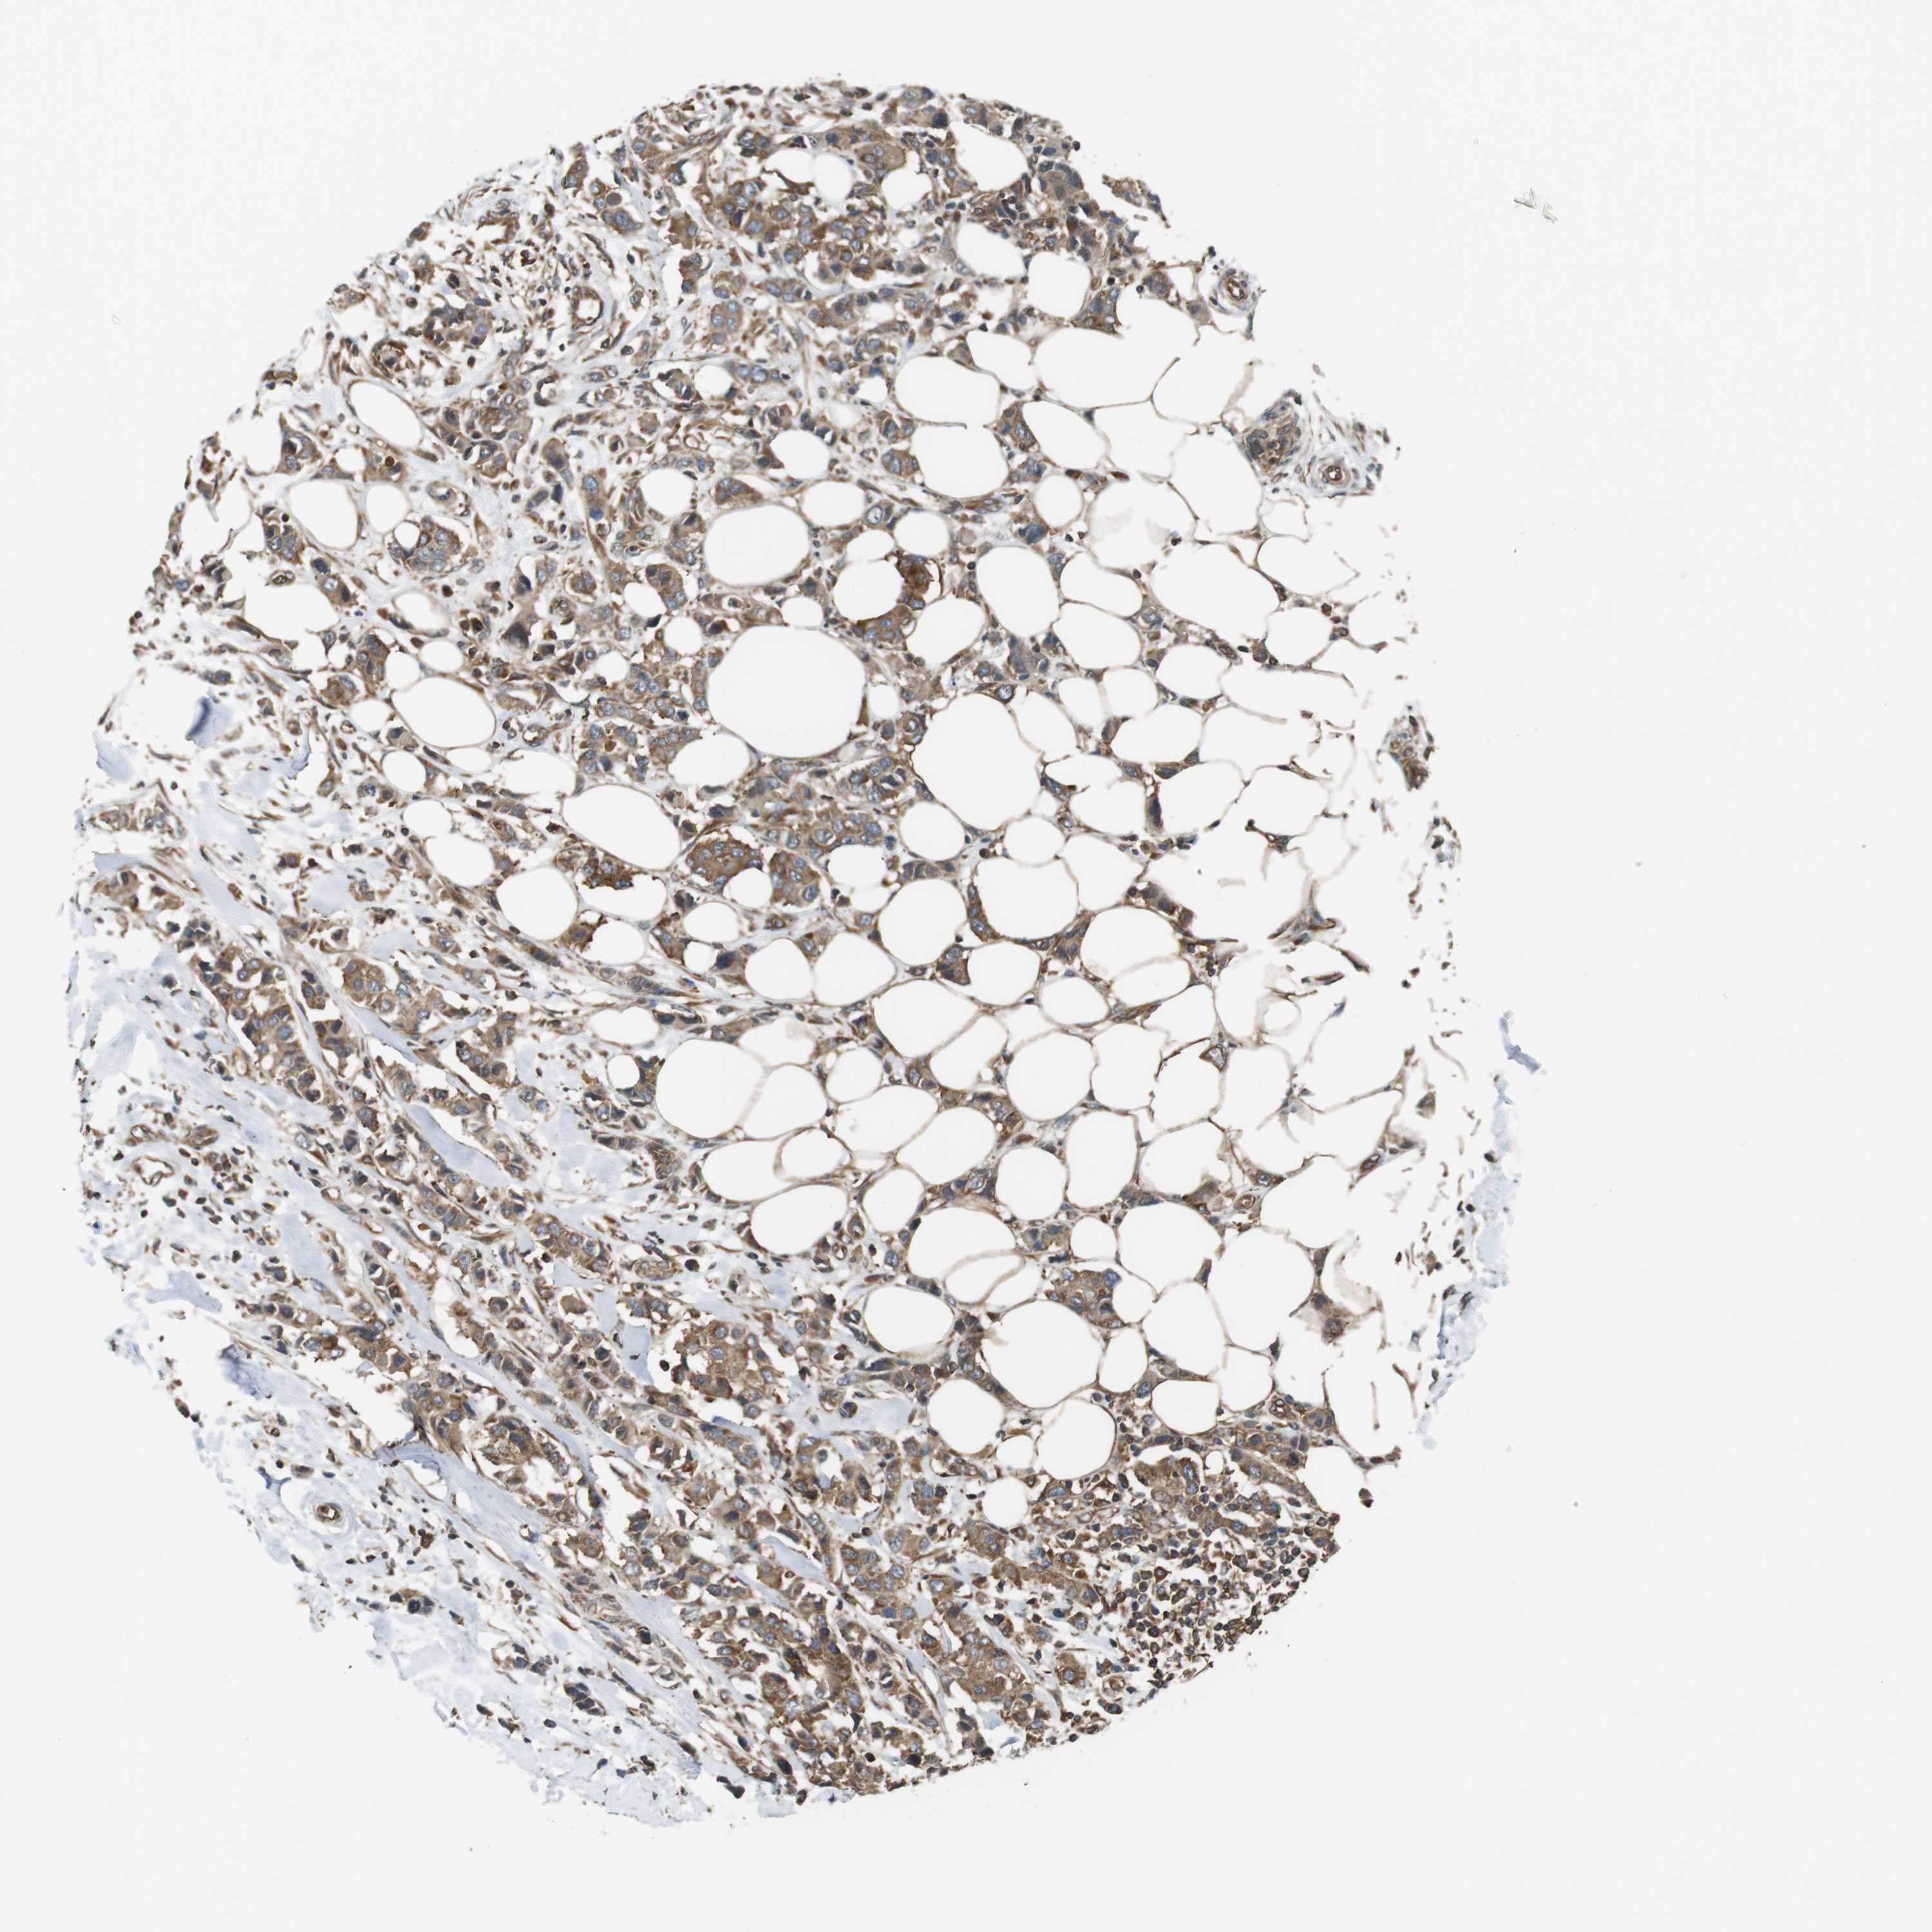

CANCER BREAST CANCER Show tissue menu

Breast cancer

Human cancer